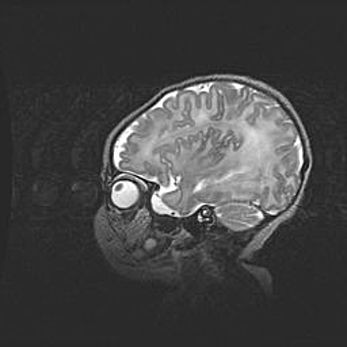

Наружная гидроцефалия с возможной атрофией височных областей.

Возраст: 28 дней

Вес: 3670 г

Пол: мужской

Окружность головы: 38 см

Срок гестации: 40 недель

Гидроцефалия головного мозга у новорожденных – это заболевание, которое характеризуется скоплением избыточного количества спинномозговой жидкости в желудочковой системе головного мозга в результате затруднения её перемещения от места выработки к месту поглощения в кровеносную систему или вследствие нарушения абсорбции. При открытой наружной форме гидроцефалии у новорожденных расширяются и переполняются субарахноидные пространства.

При нормотензивных  формах,  которые,  как  правило,  являются  следствием  перенесенных ишемических  повреждений  паренхимы  мозга,  возможно  сочетание микроцефалии  с нормотензивной гидроцефалией. В основе данных изменений лежит атрофия больших полушарий с преимущественной  локализацией  в  лобно-височных  областях.